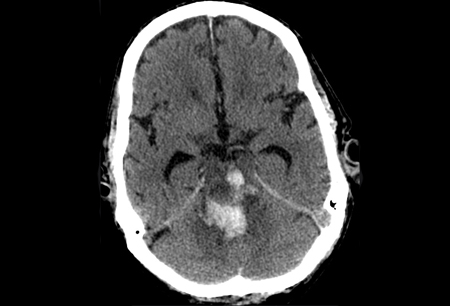

Meduloblastoma: vista sagital de ressonância nuclear magnética (RNM) mostrando uma lesão sólida e cística com ávido realce ao contraste que preenche o quarto ventrículo; presença de hidrocefalia obstrutiva

Do acervo de Peter B. Storm; usado com permissão